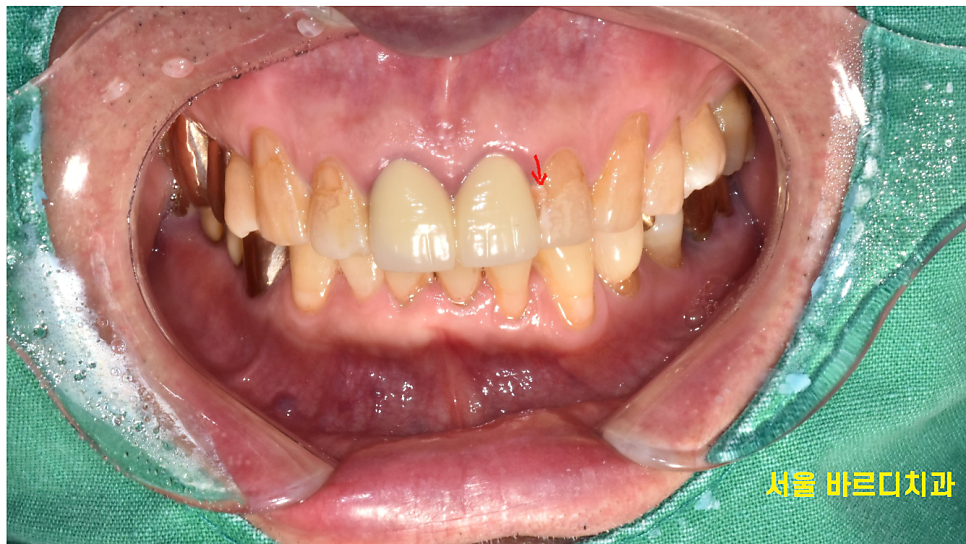

실제 구강을 살펴보았습니다.

231127

해당하는 치아에 치태도 많이 붙어있고

구멍도 나 있는 상태였습니다.

충치를 제거하고 치료를 해줘야하는데..